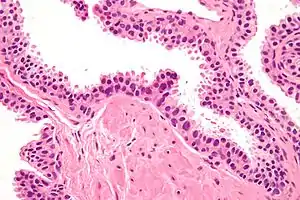

| Micrograph showing high-grade prostatic intraepithelial neoplasia. H&E stain. | |

Its cytologic features are that of prostatic adenocarcinoma:

- presence of nucleoli,

- increased nuclear-to-cytoplasmic ratio and,

- increased nuclear size.

Microscopically, PIN is a collection of irregular, atypical epithelial cells. The architecture of the glands and ducts remains normal. The epithelial cells proliferate and crowding results in a pseudo-multilayer appearance. They remain fully contained within a prostate acinus (the berry-shaped termination of a gland, where the secretion is produced) or duct. The latter can be demonstrated with special staining techniques (immunohistochemistry for cytokeratins) to identify the basal cells forming the supporting layer of the acinus. In prostate cancer, the abnormal cells spread beyond the boundaries of the acinus and form clusters without basal cells. In HGPIN, the basal cell layer is disrupted but present. PIN is primarily found in the peripheral zone of the prostate (75-80%), rarely in the transition zone (10-15%) and very rarely in the central zone (5%), a distribution that parallels the zonal distribution for prostate carcinoma.[6]